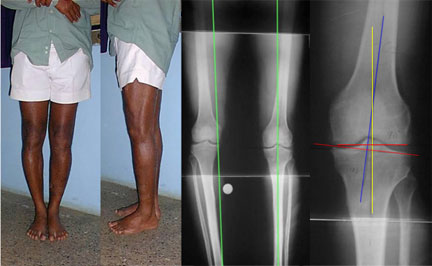

The final result as shown in the clinical pictures, full length x-ray and spot film of the knee.

The full length x-ray (second from right) confirms the mechanical axis is central again on the left side whereas the unoperated side axis is passing medial to the knee.

The spot film (extreme right) confirms a 5º femoro-tibial valgus angle (normal femoro-tibial angle is 3-5º).